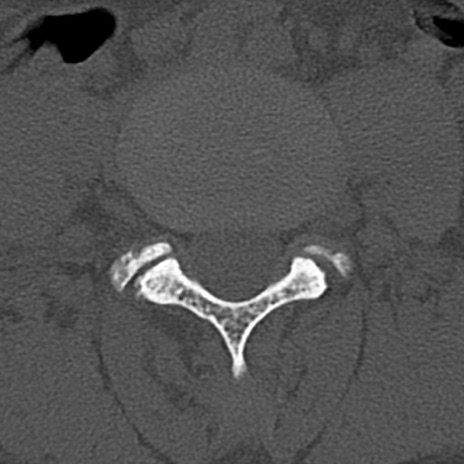

【整形】TIPS症例4 腰椎CT(横断像)

腰椎CT

横断像と矢状断像